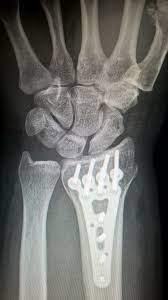

- 컴퓨터 단층 촬영 (CT 스캔): CT 스캔은 X-레이와 유사하지만 목 부위의 구체적인 문제를 더 자세히 보여줄 수 있습니다. 특히 디스크 헤르니에이션과 같은 구조적인 문제를 확인하는 데 유용합니다.

- 수술 치료는 통증이 심하거나 기타 치료 방법으로 증상을 관리할 수 없는 경우에 고려됩니다. 수술은 디스크 헤르니에이션 제거, 디스크 교체 등의 형태로 수행될 수 있으며, 종종 열린 수술 또는 미세 수술 접근법으로 수행됩니다.